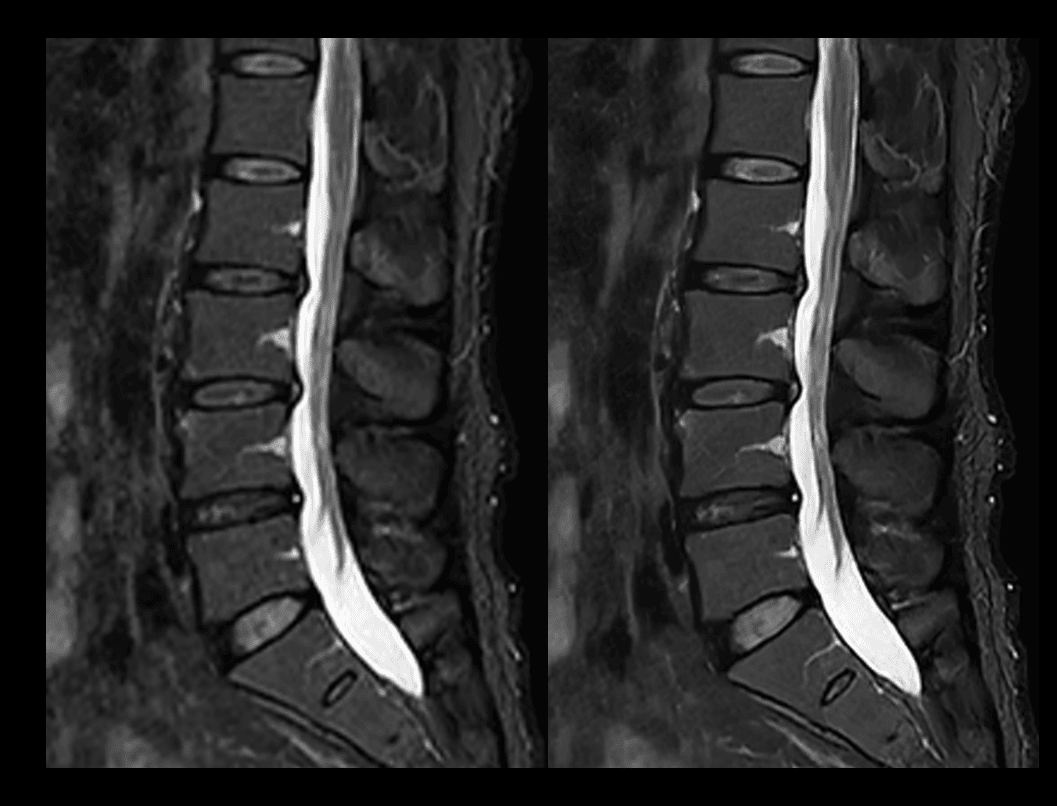

Coloană vertebrală T2W STIR

Comparație între tehnica convențională (2:44 min) și uAIFI DeepRecon™ (2:44 min), cu rezoluție de 1,11 × 1,11 × 4 mm³, demonstrând imagini mai clare și detalii anatomice superioare prin reconstrucția bazată pe AI.